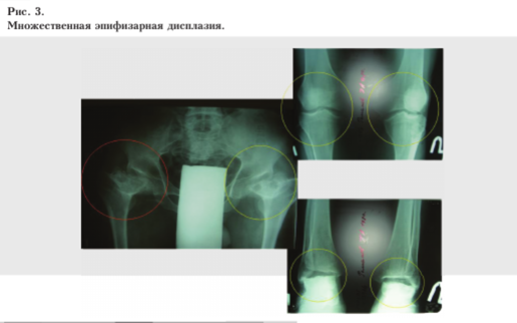

- множественная эпифизарная дисплазия (болезнь Майербанка) — 1 больной (рис. 3, 4, 5)